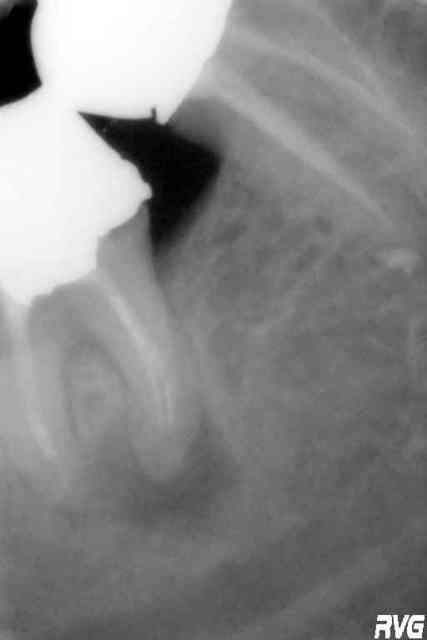

au lieu de penser donne moi un conseil pour sortir la mèche

Une astuce qui parait farfelue, mais qui te permettra certainement de la retirer sans difficulte.

Ouvre correctement la cavite d'acces,

degage l'instrument sur trois ou 4 millimetres avec des ultra sons

Utilise une grosse aiguille dont le diametre interne correspond a peu pres a celui de l'instrument. Une grosse aiguille type intra veineuse peut faire l'affaire, quoique j'ai un doute pour un F3; sinon tu trouveras ton bonheur dans les embouts de Bisico ou d'etching par exemple.

Assure toi qu'il peut s'enficher sur l'instrument

Si tu as de la resine calcinable, prepare en un peu et remplit l'interieur de l'aiguille avec

place l'aiguille remplie de resine sur l'instrument, et attend 5 minutes minimum. quand la resine a polymerise, tourne lentement l'ensemble dans le sens inverse des aiguilles d'une montre, et l'instrument va se devisser.

Si tu n'as pas de resine, tuu peux faire la meme chose avec de colle cyanoacrylate. Le temps de prise est un peu plus long. Pour l'accelerer tu peux egalement rajouter dans la cavite d'acces une goutte de monomere de resine une fois que l'aiguille est en place.

Cette technique parait un peu OLE OLE, mais elle se prete reellement a cette configuration; et finalement, ce n'est pas le plus difficile a retirer.

D'apres mon confrere le Dr. Vafancullo; si tu ouvres correctement ta cavité, degages 2 ou 3 mm a la fraise de touati autour de ton protaper, il se pourrait meme que les US à fond les manettes suffisent .

Parce qu'une fois bien accessible dans l'axe; il est qd meme peté tellement haut qu'on croirait un screw-post

US et fraise, c'est vraiment pour le cas de depart cassé extremement haut